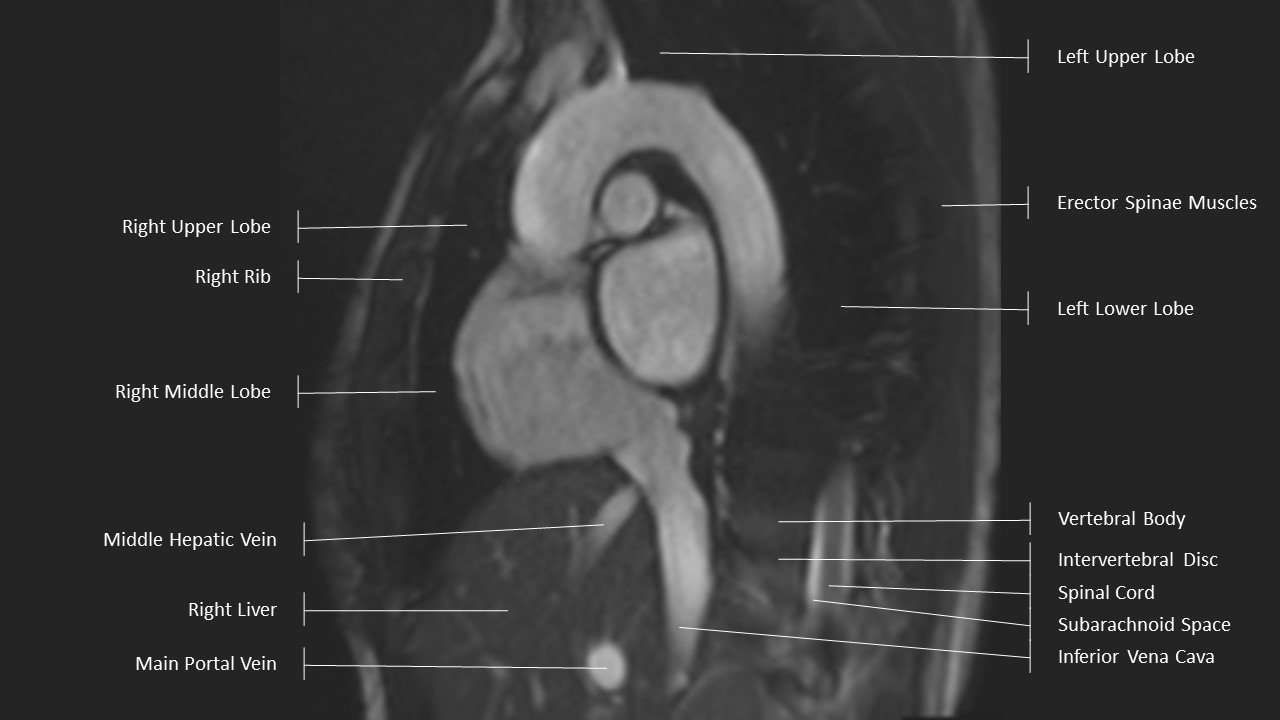

Aortic Arch Series